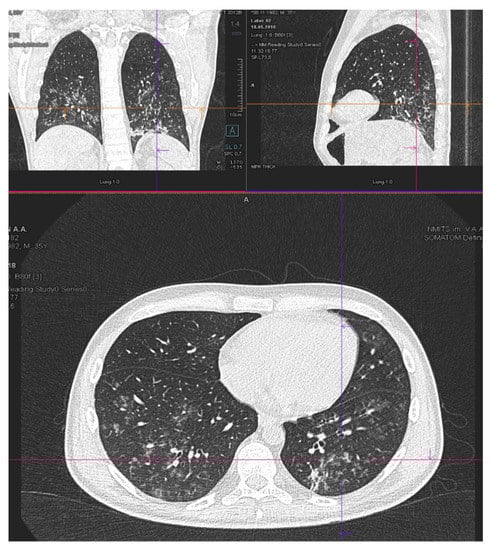

| Patient status before GO therapy initiation | The WHO performance status of 3. Marrow blast cells 88.6%, peripheral blood blast cells 60%, pancytopenia grade 3–4. CRP was slightly increased to 20 mg/L. Acute kidney failure grade 2 with no prior history of chronic kidney disease dehydration, use of nephrotoxic agents or tumor lysis syndrome signs. Creatinine increasing up to 2.8xULN and GFR decline to 15 mL/min. | The WHO performance status of 3. Marrow blasts cells 68%. High fever and elevated CRP level up to 332 mg/L with no response to escalated antibiotics/antimycotics combination. The patient had respiratory failure grade 2 with massive bilateral polysegmental lung infiltrates according to a chest CT scan. |

| On day 5 after GO infusion «GO+Aza» therapy was initiated. No laboratory signs of kidney injury were noticed during whole period of therapy in the «GO+Aza» regimen. | A chest CT scan on day 6 of the GO therapy showed a significant regression of pulmonary infiltrates in the size. | |